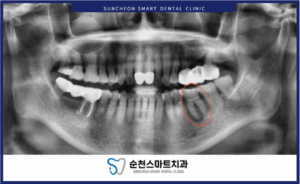

처음 내원하셨을 파노라마 방사선 사진으로 관찰한 결과,

왼쪽아래(사진에서 오른쪽) 큰 어금니 뿌리 쪽에

치조골 흡수와 더불어

염증이 매우 크게 있었습니다.

사진에서 표시된 부분을 보시면,

유독,

그 부분만 다른치아들 치조골에 비해

뿌리를 둘러싼 뼈의 색이

검게 보이는데요.

치조골이 약해지면

뼈의 두께가 감소하기 때문에

방사선이 투과하여

얇아진 것을 확인 할 수 있습니다.